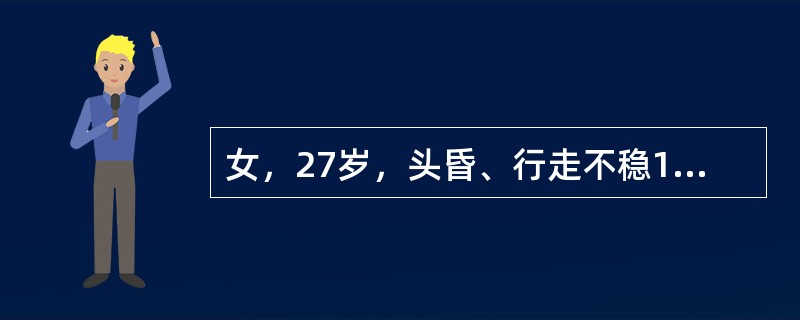

女,27岁,头昏、行走不稳1个月,PE:指鼻试验(+),Romberg氏征(+),根据所提供图像,最可能的诊断()

A.左小脑脓肿

B.左小脑血管母细胞瘤

C.左小脑星形细胞瘤

D.左小脑胶质细胞瘤

E.左小脑转移瘤

女,27岁,头昏、行走不稳1个月,PE:指鼻试验(+),Romberg氏征(+)

[单选题]女,27岁,头昏、行走不稳1个月,PE:指鼻试验(+),Romberg氏征(+),根据所提供图像,最可能的诊断()A . 左小脑脓肿B . 左小脑血管母细胞瘤C . 左小脑星形细胞瘤D . 左小脑胶质细胞瘤E . 左小脑转移瘤